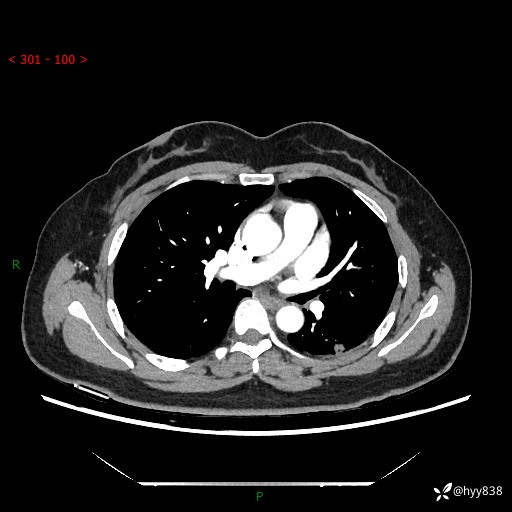

胸部CT复查+增强(2024.6)